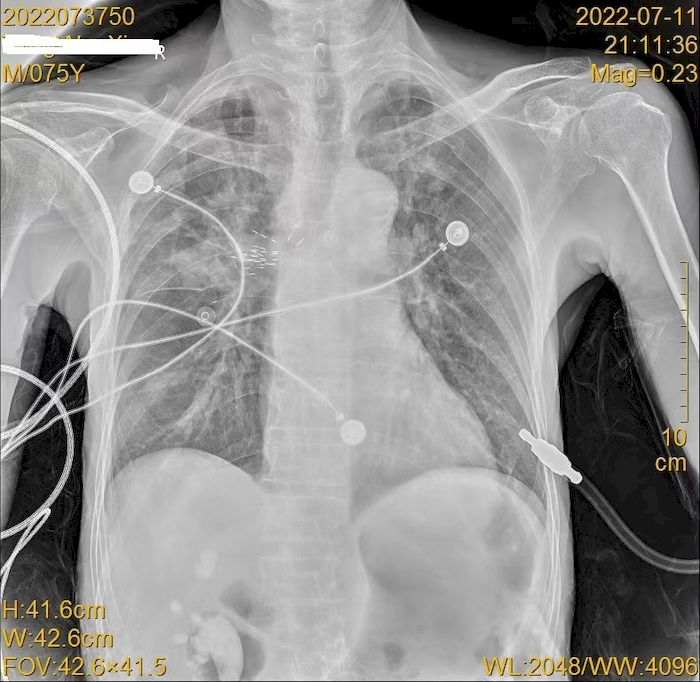

放射性粒子植入术后复查胸片查看粒子位置。于涛供图

经过详细准备,7月11日,在麻醉科及内镜中心团队大力支持和配合下,呼吸内科副主任医师李文利、于涛成功为汤先生实施了全麻下经超声支气管镜下放射性粒子植入术。即在麻醉成功后经喉罩进镜,经依靠超声支气管镜定位病灶,测量病灶大小,做好术中手术规划,在超声支气管镜引导下穿刺植入放射性粒子(碘125)36粒,手术顺利,术后患者安返病房,并于术后第二天出院。

据赵磊介绍,放射性粒子植入治疗的全称是“放射性粒子组织间插植术”,是一种近距离放射,精确治疗肿瘤的新技术。它的原理是把微放射源在影像(CT或超声)、内镜的引导下植入肿瘤,使肿瘤得到一个高度适形、高度调强的治疗手段。它在肿瘤局部形成高剂量放疗,但肿瘤周围的脏器并不会受到伤害。医师依据事先制定的治疗计划,在影像或内镜超引导下,将放射性粒子准确植入肿瘤靶区,放射性粒子在体内持续不断发出射线,可使肿瘤接受的剂量明显增加,达到高剂量靶区适形治疗,由于是持续性低剂量率的照射,能对不同成熟度的肿瘤细胞进行不间断的照射,增加了放射生物效应,提高放疗疗效,改善气道功能,提高患者生活质量。(曹亚 于涛)